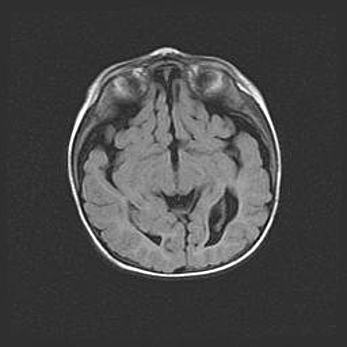

Лейкомаляция с кистозно-глиозной дегенерацией головного мозга.

Возраст: 2 месяца 25 дней

Вес: 6400 г

Окружность головы: 40 см

Срок гестации: 41 неделя

Лейкомаляцию относят к ишемически-гипоксическим повреждениям головного мозга, диагностируемым у новорожденных. При лейкомаляции в головном мозге обнаруживают очаги некроза, возникшие после тяжелой гипоксии и нарушения кровотока. В процессе морфогенеза очаги проходят три стадии: 1) развития некроза, 2) резорбции и 3) формирования глиозного рубца или кисты. Перивентрикулярная лейкомаляция (ПЛ) встречается примерно в 12% случаев среди новорожденных, обычно – у недоношенных детей, причем, частота ее зависит от массы, с которой младенец появился на свет. Наибольшее число малышей страдает лейкомаляцией, если масса при рождении 1500-2500 г.